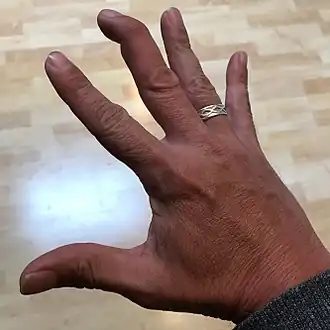

A Busch fracture, showing the characteristic mallet finger

A Busch fracture, showing the characteristic mallet finger -